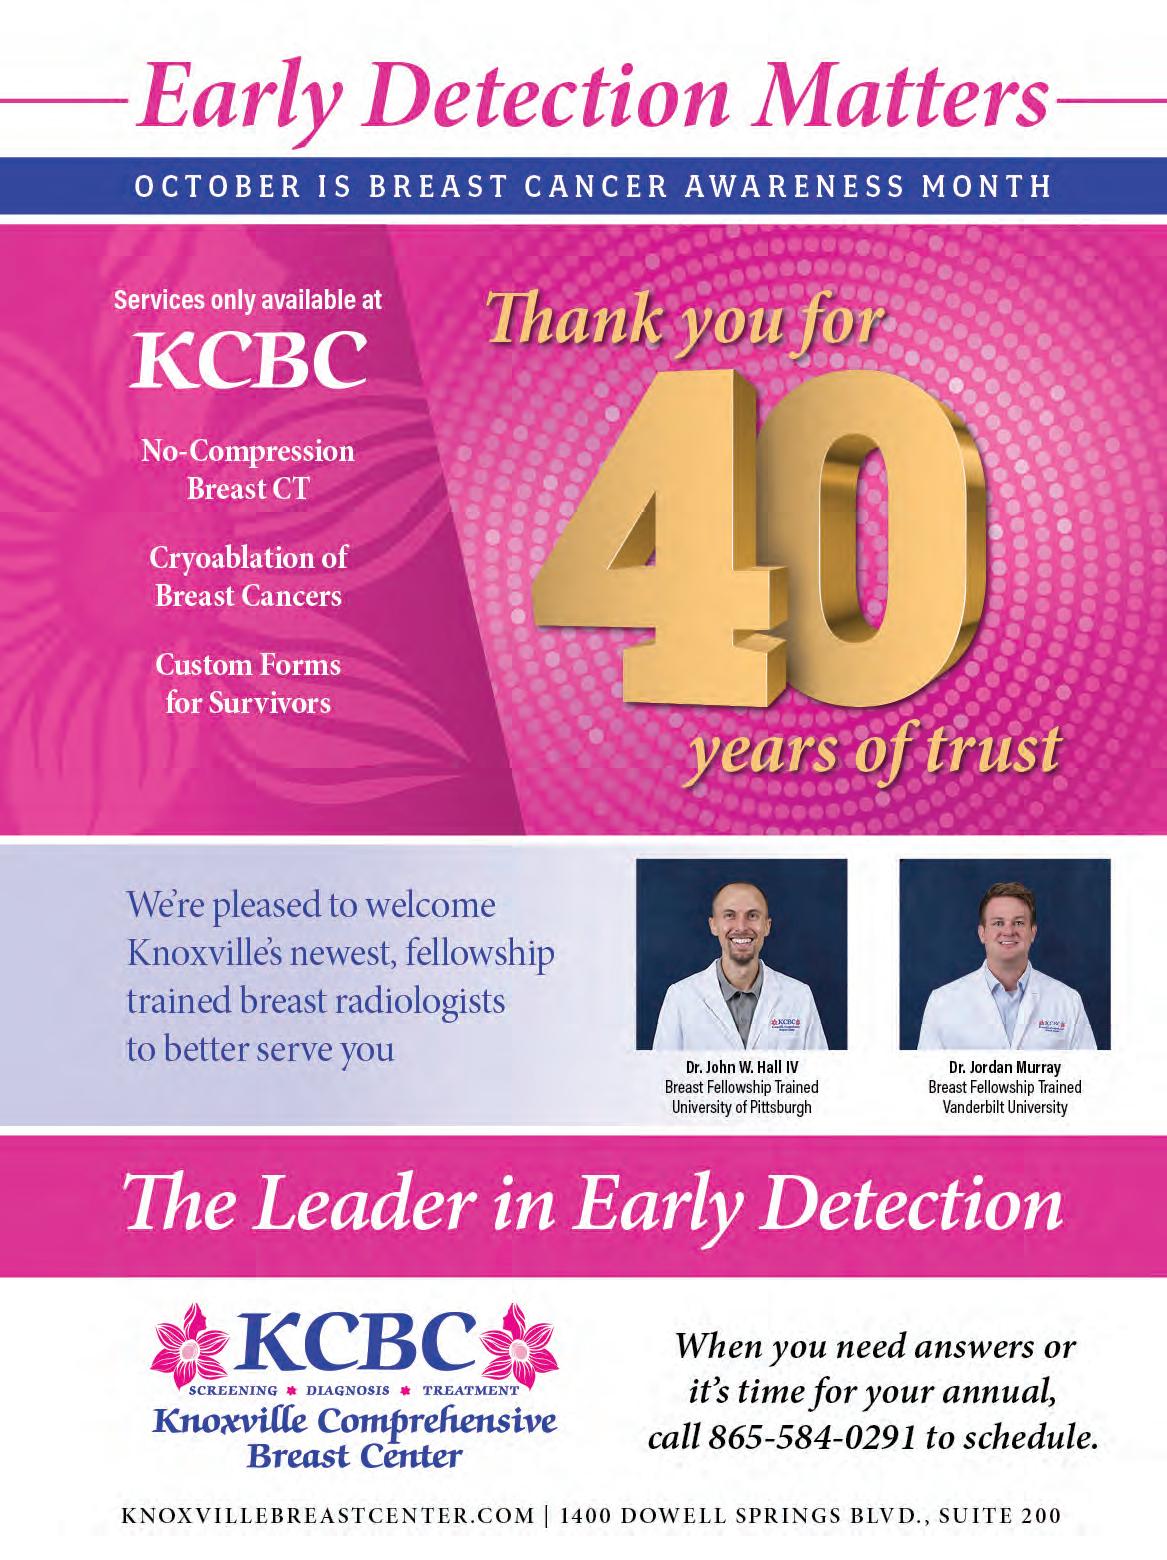

East Tennessee Children’s Hospital is committed to providing excellent pediatric care, offering help to every family and bringing healing to our region. We understand that providing the best care for your child means more than just treating their illness or injury. Our team of specialized pediatric healthcare professionals cares for the whole child and provides expert, customized care plans for your family.